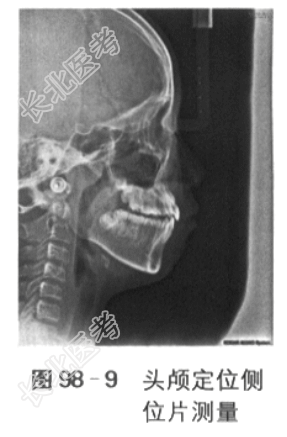

[材料题] 一、病历资料:1.主诉前牙“地包天”3年,牙齿不齐,要求矫治。2.现病史患者男性,10岁,前牙反咬,“地包天”3年余,自觉牙齿不齐,影响美观,要求矫治。否认吐舌、吮指、咬上唇等不良习惯史,否认口呼吸史。3.既往史患者乳牙合期有“地包天”史,未进行相关治疗。否认外伤史,否认家族史。否认系统疾病史。4.临床检查(1)正面观:面部基本对称,下颌无偏斜。(2)侧面观:凹面型,下唇外翻。(3)颞下颌关节检查:张口度、张口型正常,双侧颞下颌关节未及弹响,无压痛。口内检查:混合牙列,上颌654c21~12c456,下颌76E4321~67,6近中关系,16、12、11、21、22、26反,反覆盖浅,反覆深,下中线左偏2mm,上牙弓狭窄,上前牙直立,重度拥挤,15腭侧错位,14、24颊侧错位,下颌3~3重度拥挤,22过小牙,口腔卫生良好,牙周健康。下颌可后退至切对切(见图98-1)。5.影像学检查6.模型分析(1)上牙弓拥挤度:未测量(13、23阻萌,15腭侧错位,重度拥挤)。(2)下牙弓拥挤度:4mm。(3)下颌Spee曲度:4mm。(4)前牙Bolton比:80.3%。(5)全牙Bolton比:92.7%。二、诊断与诊断依据:(1)骨性Ⅲ类,上颌轻度发育不足,下颌轻度发育过度:头颅定位侧位片测量值显示SNA78°,SNB80°,ANB-2°,Ao-Bo-8mm,APDI95°。(2)安氏Ⅲ类:前牙反,第1恒磨牙近中关系。(3)牙列拥挤:全景片显示上颌双侧尖牙阻萌,模型测量显示下颌拥挤度为4mm,上颌15腭侧错位。(4)13、23阻生可能。